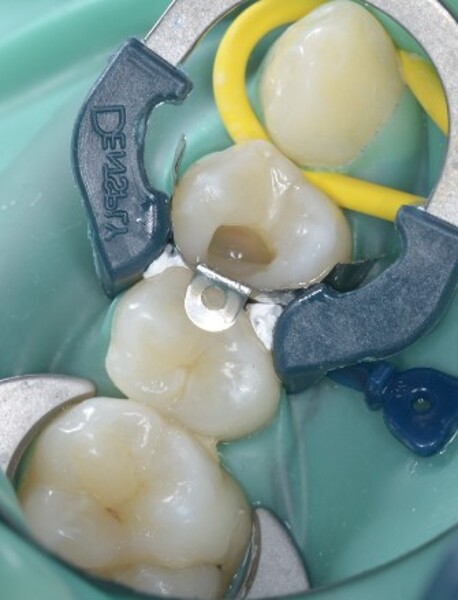

Predictable posterior restorations